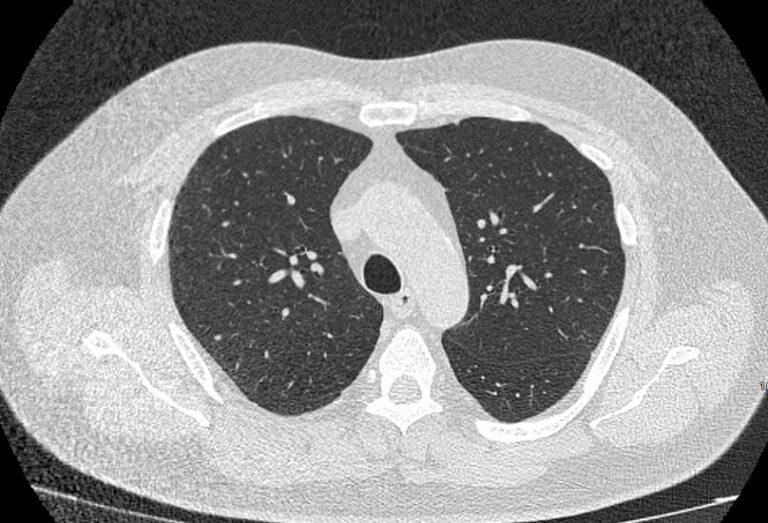

Во время исследования рентгеновская трубка томографа вращается вокруг исследуемой области и производит множество послойных снимков с шагом 0,5-1 мм. Полученные снимки поперечного сечения с помощью компьютерной программы могут быть преобразованы в 3D-изображения исследуемого органа или участка ткани. Это позволяет выявлять практически все заболевания легких на ранних стадиях и назначать своевременное лечение.

В медицинском центре «Доступная медицина» используется современный 128-срезовый компьютерный томограф TOSHIBA AQUILION CXL, на котором проводится сканирование легочной ткани. За счет увеличенного количества детекторов аппарат производит снимки с большой скоростью и минимальной дозой облучения. При этом инновационные цифровые приложения позволяют получить объемные изображения легочной ткани высокой четкости, контрастности и в мельчайших подробностях.